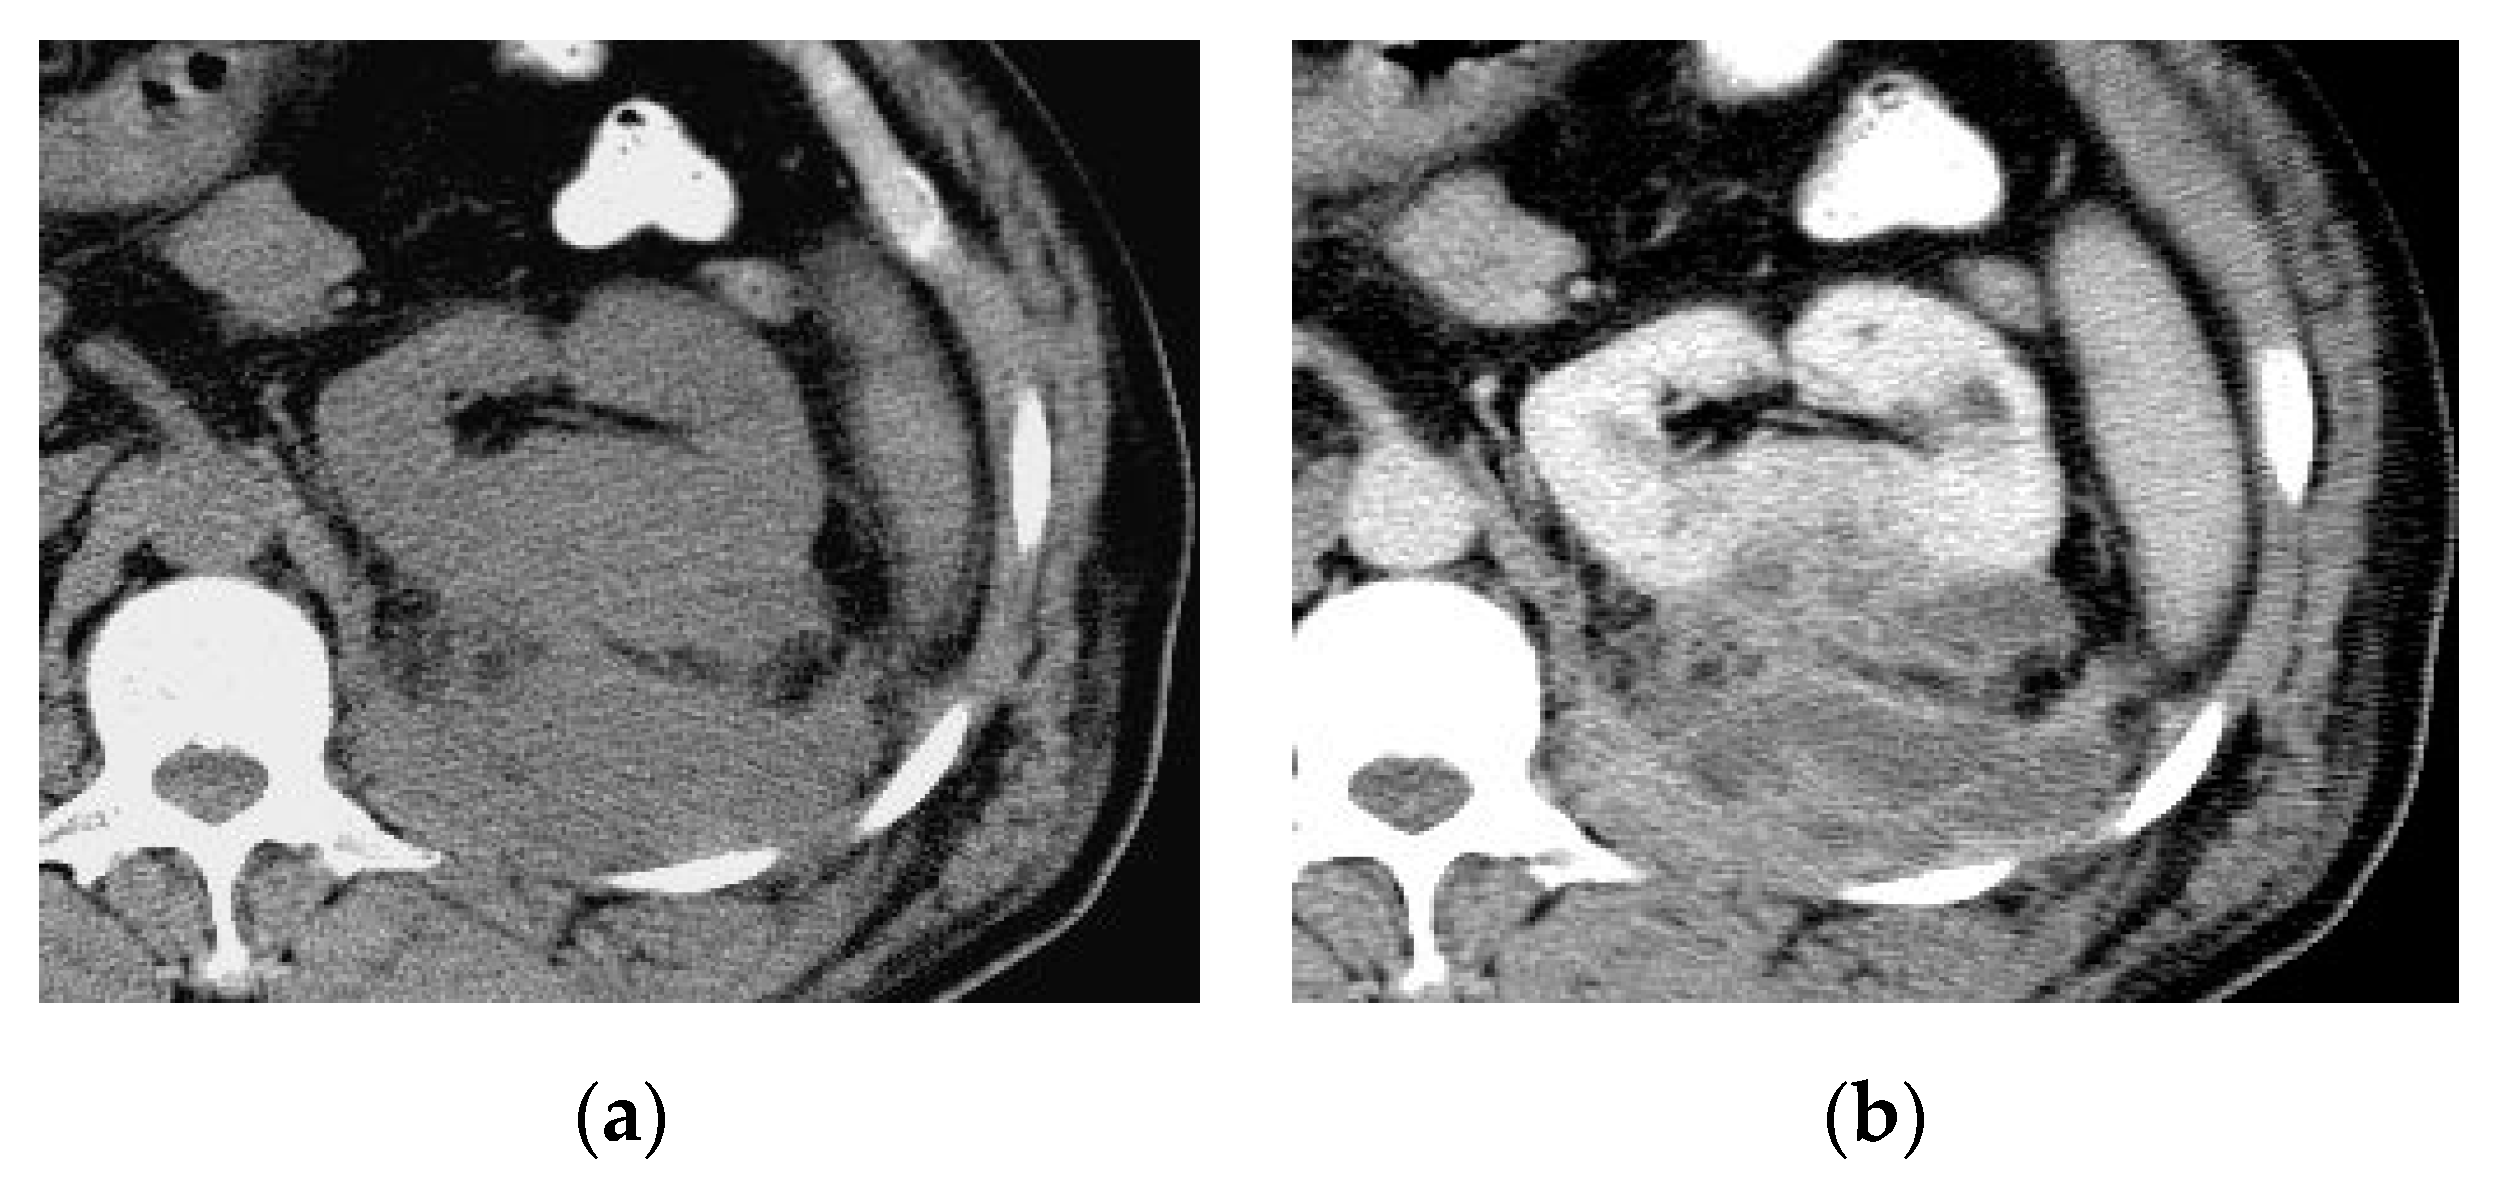

2.2. Renal and Perinephric Abscesses

| Renal abscesses | Round or geographic non-enhancing central fluid collection and enhancing rim. Perinephric fat stranding and thickening of Gerota’s fascia. |